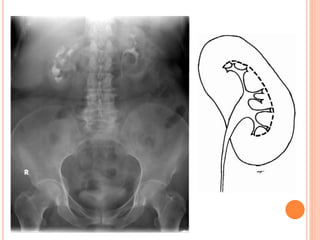

 Evaluation of the PCS.

- Obstruction (round

forniceal margin).

- CM inside the papillae.

- Parenchymal cavities

filled with CM.

- Filling defect.

- Phantom calyx.